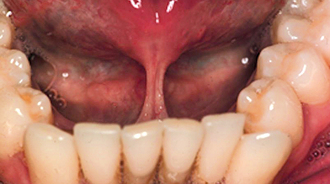

Attempts should be made to retain the keratinized tissues by employing displacement of the attached gingiva with apically or, occasionally, laterally repositioned flaps. The apically repositioned flap retains the mucogingival collar around the tooth and is displaced apically and sutured into place. The bunched gingiva will remodel as wound healing occurs (Fig. 12.1). If the tooth is misaligned, a bracket and gold chain may be etched to the canine to direct its eruptive path appropriately (Fig. 12.2).

Fig. 12.1 An erupted canine 3 months after exposure using an apically repositioned flap. The irregular gingival contour will gradually diminish with the passage of time.